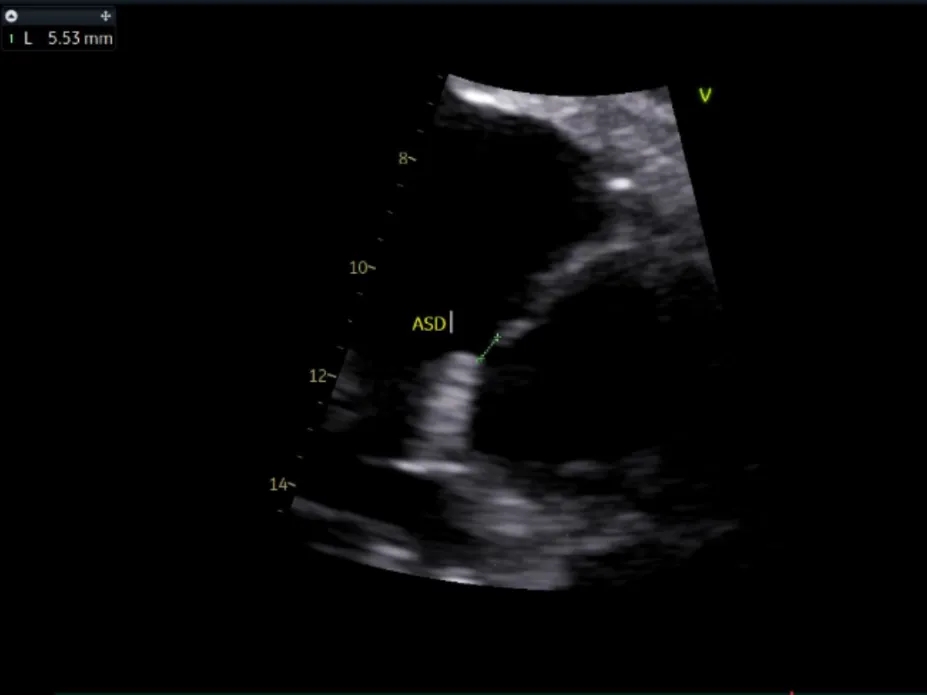

术中复测

左室长轴切面及四腔心切面复测缺损直径均约6mm